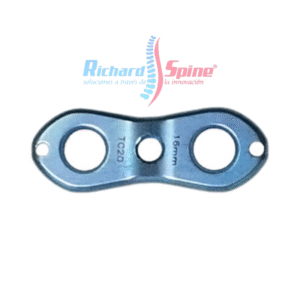

Placa de Fusión intercorporal cervical anterior

- La placa de fusión intercorporal cervical anterior es un dispositivo metálico utilizado en cirugía para estabilizar la columna cervical, específicamente en procedimientos de fusión intersomática anterior (ACIF). Esta placa se coloca en la parte frontal de las vértebras cervicales, después de la extirpación de un disco intervertebral dañado, para mantener la alineación y promover la fusión ósea entre las vértebras.